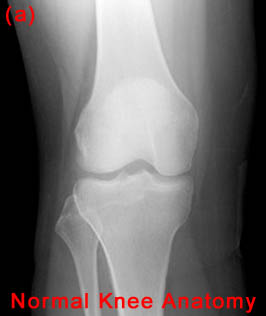

27) A patient is known to have a torn ACL and presents for x-ray examination of the knee. Which of the following abnormalities is often associated with a torn ACL?

"B&C" - Both Segond fractures and tibial plateau fractures are commonly associated with ACL tears.